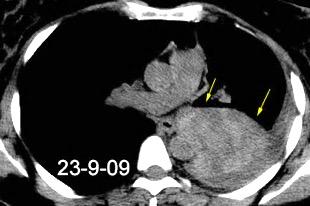

40. EMPIEMA PLEURAL. ORIGEN HEPÁTICO

Colecciones “inflamatorias” abdominales llegan al tórax vía el hiato esofágico o por vía transdiafragmática

Afectación transdiafragmática: 5,6-43,7% de quistes hepáticos. “Área desnuda” del hígado.

Panda A et al. “Straddling Across Boundaries”. Thoracoabdominal Lesions: Spectrum and Pattern Approach. Curr Probl Diagn Radiol. 2015 Área desnuda. El hígado en contacto directo con el tendón central del diafragma. Contiene el hiato de VCI.